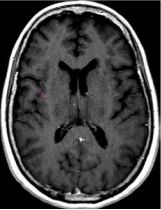

一位77岁的女性患有EPS15-NTRK1 IV期非小细胞肺癌,我们可以看到她的双肺满是病灶,并且出现了肝脏和脑转移,可以说是非常非常晚期了,

肺靶病变达到缓解,我们可以明显的看到前后的图像,病灶明显缩小了,

脑转移病变显示缩小了95%!

初始, 2018年6月             3周期 2018年8月